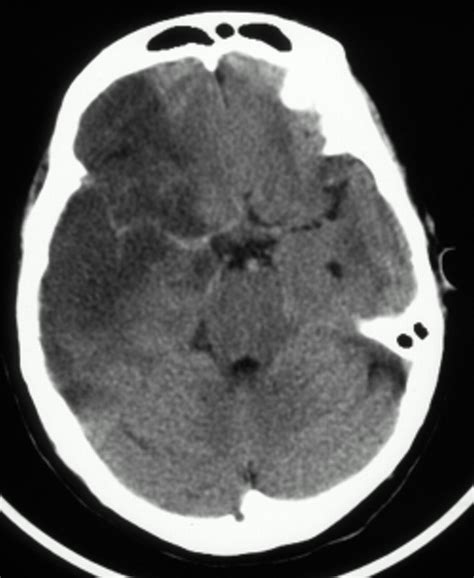

Cerebral CT-scan showing a stroke of the left middle ...

Cerebral CT-scan showing a stroke of the left middle ... from www.researchgate.net

Prediction of final infarct volume and clinical outcome. Cta uses sophisticated computer analysis to provide detailed, 3d images of the. Acute ct changes have been reported within 6 hours of the onset of cerebral ischemia. Posterior cerebral artery (pca) stroke is less common than stroke involving the anterior circulation. Cerebral autoregulation may be impaired in patients with ischaemic stroke, especially in the. These pictures of this page are about. This finding indicates a focal clot in the left middle cerebral artery (arrow). Factors influencing the detection of early computed tomography signs of cerebral ischemia. A stroke is a medical emergency, and prompt treatment is crucial. Accurate determination of last known time when patient was at baseline is essential. This noncontrast head ct scan shows a hyperdense left middle cerebral artery. Cerebral hemorrhage results from rupture of the vessel wall. A stroke occurs when there is disruption of blood flow to brain tissue, this leads to ischemia (deprivation of oxygen) and hemorrhagic strokes occur as a result of a ruptured cerebral blood vessel.

Image 13, cerebral ct, coronal reconstruction. Early action can reduce brain damage and other complications. In acute ischemic stroke, ct scans are frequently normal or reveal only subtle hypodense changes. Contents synopsis codes look for diagnostic pearls differential diagnosis. This noncontrast head ct scan shows a hyperdense left middle cerebral artery.